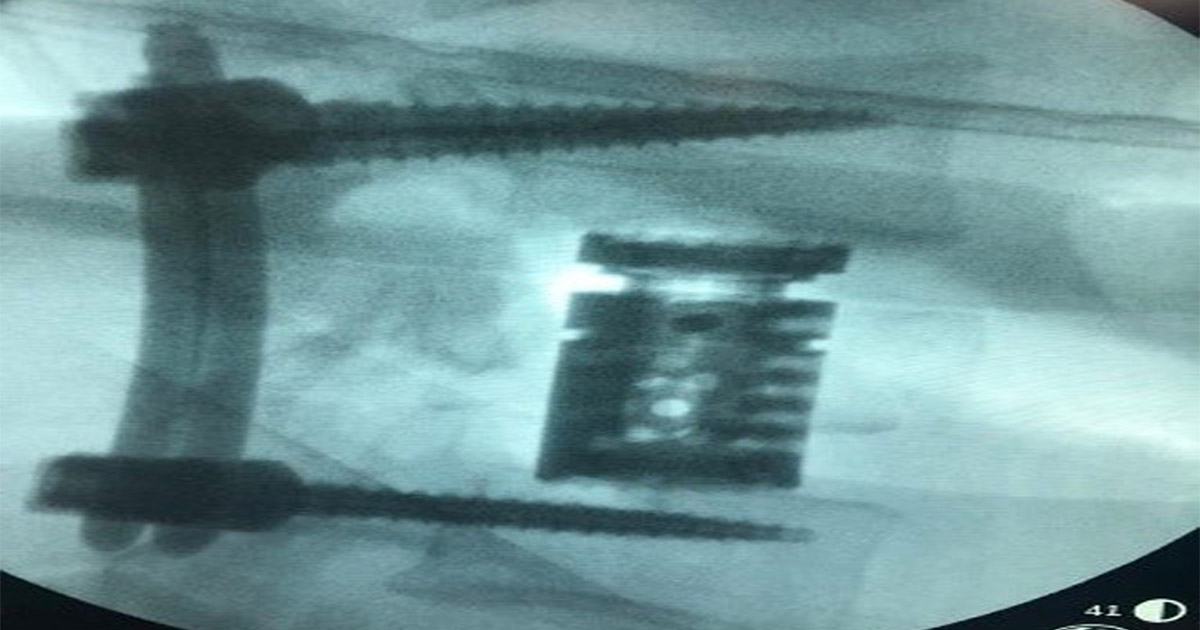

Por lo cual a este paciente de 25 años se realiza procedimiento quirúrgico donde la junta médica definió y se autoriza colocación en decúbito lateral N bloque para evitar úlceras por presión. Además, se hace restauración anatómica por distracción intravertebral de L1, fijación transpedicular de L2-L4 percutánea, vertebrectomia de L3 vía anterolateral con colocación de cilindro expandible. Por último, neurocirugía por artrodesis L2-L4 posterior más corpectomia anterior de L3 más restauración anatómica de L1.